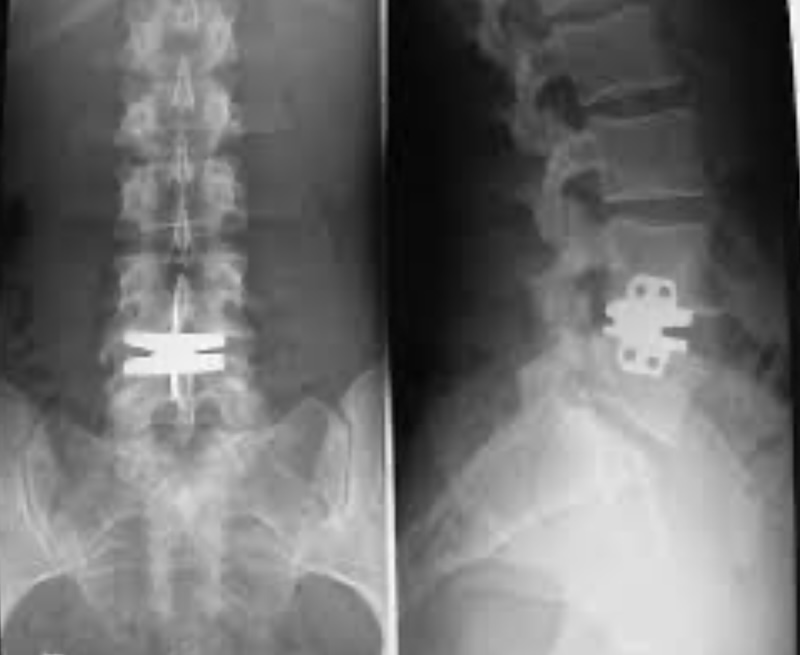

Maverick Lumbar Artificial Disc

The Maverick Lumbar Artificial Disc was a pre-FDA lumbar disc arthroplasty developed by Medtronic. The disc is a 2-piece metal-on-metal disc composed of Cobalt-chrome. The endplates are composed of titianium plasm sprayed and featured a central keel for fixation.